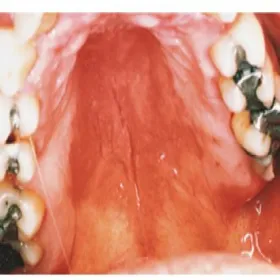

grzybica podniebienia